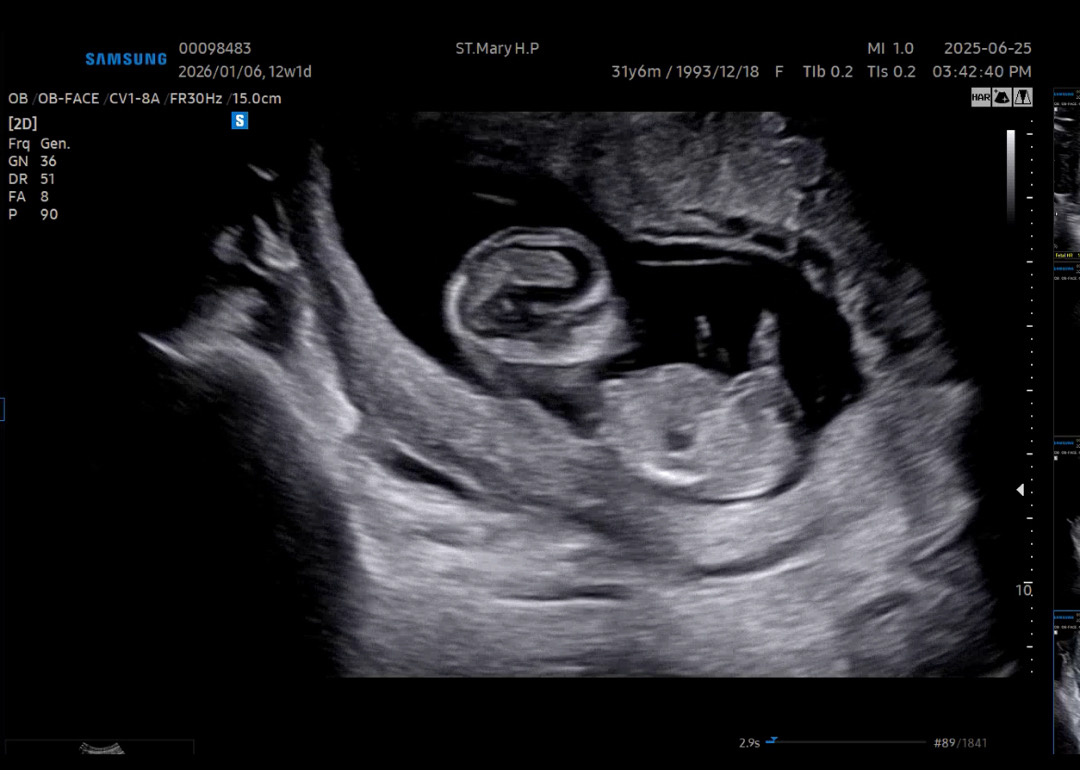

12주 1일차 각도법 확인부탁드려용~~

오늘 입체초음파 검사받고 왔는데 성별 가늠이 안되네요 ㅠ 이 사진으로 성별 확인이 될까요?

알기어렵네용 저건 다리같은데 다리아닌가용

이사진으론 알 수 없어용